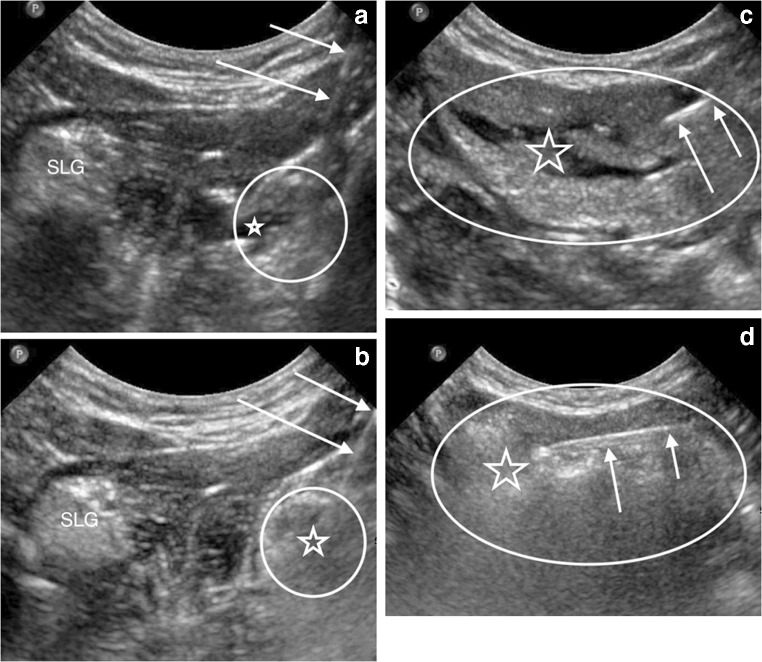

The submandibular and sublingual glands were ablated using a 21- to 25-gauge needle that was advanced percutaneously from under the chin into the glands under direct US visualization. Un-foamed STS was injected throughout each gland while visualizing liquid distribution with US (Fig. 2). After a brief delay, EtOH was delivered in a similar fashion (Fig. 2). Care was taken to puncture the gland capsule as few times as possible. Drug volumes were determined by subtracting the residual syringe volume from the known initial syringe volume (Table 1).

Fig. 2.

US images of the sublingual gland and submandibular gland during 3% sodium tetradecyl sulfate (STS) and 98% dehydrated ethanol (EtOH) injections in a 3-year-old girl. a Coronal US image from beneath the chin shows a needle (arrows) puncturing the right sublingual gland (circle outlines approximate margins of the gland) and injecting STS (star), which appears hypoechoic within the gland. The left sublingual gland (SLG) is labeled for comparison. b Coronal US image shows the needle (arrows) again puncturing the right sublingual gland (circle outlines approximate margins of the gland) and injecting EtOH (star), which causes immediate echogenic destruction of the gland. c US longitudinal to the submandibular gland (oval outlines the approximate margins of the gland) shows the needle (arrows) injecting STS (star), which causes the hypoechoic fissuring of the gland. d US longitudinal to the outlined (oval) submandibular shows the needle (arrows) injecting EtOH (star), which causes immediate echogenic destruction of the gland